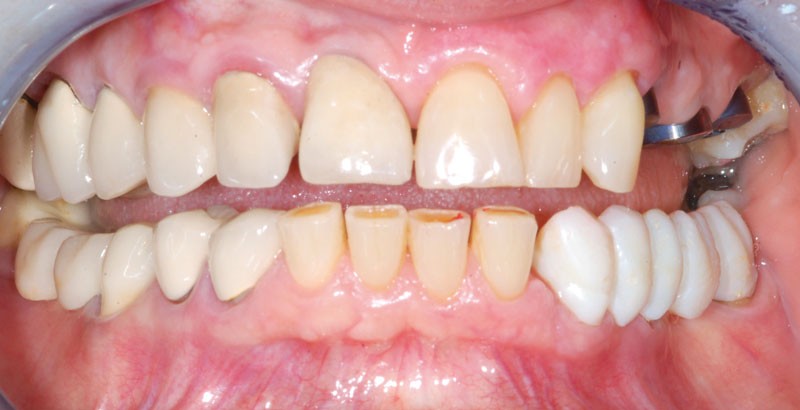

Le bridge 24-26 céramométallique et la couronne unitaire sur 27 sont réalisés. Les piliers CFAO sont transvissés sur les implants, puis les éléments céramo-métalliques sont posés. Le résultat montre un parfait respect du projet prothétique en fonction de la courbe occlusale obtenue avec le bridge transitoire réalisé avec le ProtempTM 4 et une adaptation parfaite.